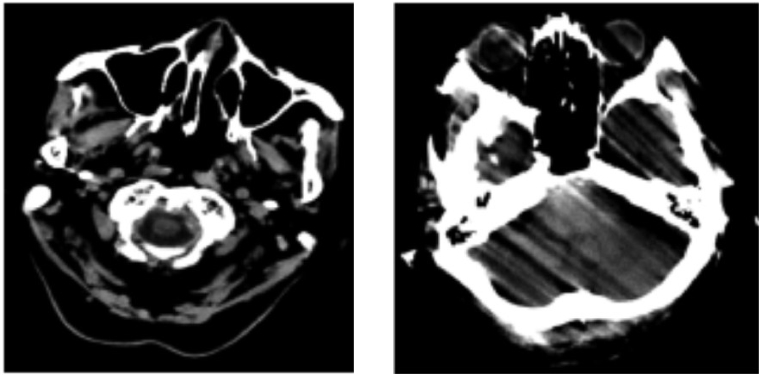

Yi-wen LIU, Tao WEN, Yuan-guo BI, Hong-bo ZHU. CT Image Quality Classification Based on Stacking Ensemble Learning[J]. Journal of Northeastern University(Natural Science), 2025, 46(11): 30-36.